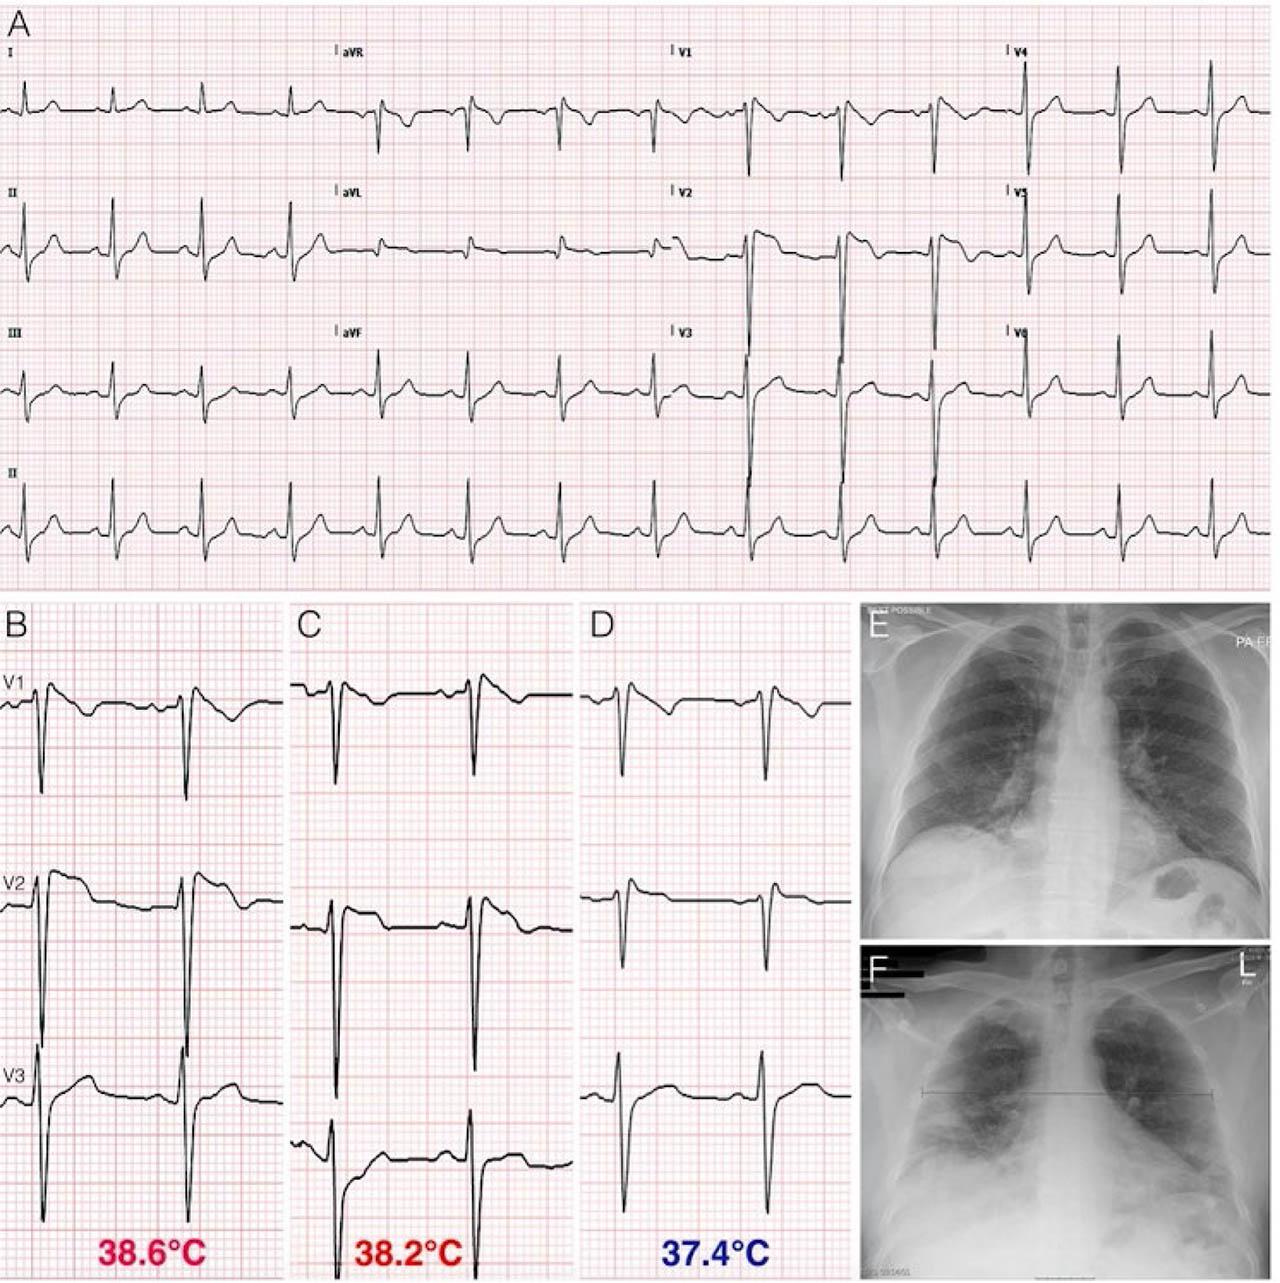

Figure 1